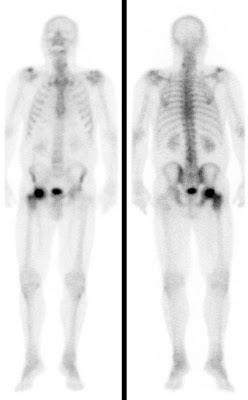

Bei der Skelettszintigraphie werden schwach radioaktiv markierte Phosphatkomplexe verabreicht, die zunächst im Blut durch den Körper zirkulieren und im Verlauf von 2-3 Stunden ausreichend in den Knochen eingebaut werden, so dass dann der Knochenstoffwechsel abgebildet werden kann.

Es bestehen die Möglichkeiten, gleich nach Verabreichung der Phosphatkomplexe die Durchblutung zu untersuchen und auf den Spätaufnahmen den Knochenumbau zu beurteilen. Bei der Skelettszintigraphie gibt es keine Unverträglichkeitsreaktionen auf die verabreichten Radiopharmaka. Im Gegensatz zu vielen Röntgenkontrastmitteln sind die verwendeten Radiopharmaka auch nicht nierenschädlich.

Die Hauptfragestellungen bei der Skelettszintigraphie betreffen die Feststellung evtl. Knochenmetastasen bei Krebserkrankungen und die Unterscheidung von primär entzündlichen vs. primär degenerativen Gelenkerkrankungen, also rheumatischen Grunderkrankungen mit Skelettbeteiligung vs. (aktivierten) Arthrosen.

Darüber hinaus ist die Skelettszintigraphie häufig auch bei der Abklärung unklarer Knochenschmerzen sehr hilfreich, etwa zur Feststellung evtl. Knochentumoren, von Prothesenlockerungen, einer Osteomyelitis, von Frakturen, von Knocheninfarkten etc.